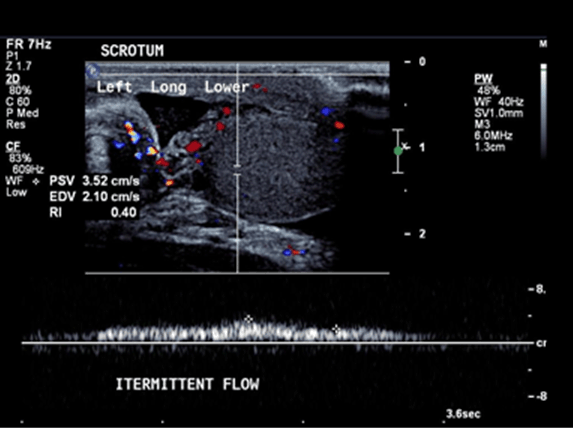

Ultrasound of the scrotum showed polyorchidism with two distinct testes within each hemi-scrotum. The upper left testis measured 3.4x2.5 cm with no Doppler flow to the testis and adjacent hyperemia in the epididymis (Figure 1). The lower left testis measured 1.7x3.3 cm with decreased Doppler flow (Figure 2). The right hemi-scrotum contained two distinct testes measured 2.3x2.6 cm in the right upper testis (Figure 3) and 3.5x3.3 cm in the right lower testis (Figure 4).

Figure 2: Left lower testis measured 1.7x3.3 cm and decreased Doppler flow to the testis.

The main finding is the presence of a mass with identical echotexture to the ipsilateral testis with the similar flow characteristics to the ipsilateral testis on the color Doppler sonography [5]. In our case, the flow to the left supernumerary testis was absent and the flow to the left ipsilateral testis was also decreased which raised the suspicion of left sided supernumerary testicular torsion.